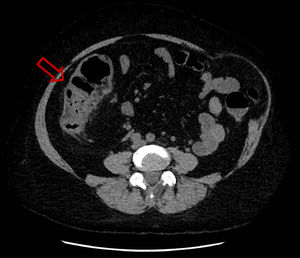

She was hospitalized for the first time because of febrile aqueous diarrhea evolving for 72 hours. A non-injected abdominopelvic computed tomography (CT) scan showed right ileocolitis (Fig. 1). First-line investigations included stool culture, parasitological examination of stools that were negative, a blood culture pair before antibiotic therapy that returned sterile, and a negative viral load for cytomegalovirus (CMV). Then, antibiotic treatment was started with 1 g of intravenous ceftriaxone once a day and 500 mg of oral metronidazole three times a day for five days, allowing the regression of symptoms and the patient was then discharged.